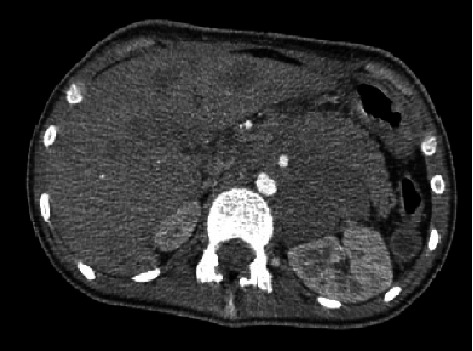

背景:食管胚胎性横纹肌肉瘤(ERMS)是一种罕见的儿童癌症,在一个涉及吞咽困难和呕吐的病例中模仿贲门失弛缓症。由于潜在的并发症,诊断和化疗需要仔细监测。病例介绍:一名12岁女孩,无既往病史,表现为进行性吞咽困难和呕吐。初步诊断为贲门失弛缓症,但进一步检查发现一个大的纵隔肿块引起食管压迫。活检证实原发性食管ERMS伴转移。尽管化疗,她出现并发症,包括中性粒细胞减少性小肠结肠炎和后部可逆性脑病综合征(PRES)。不幸的是,她死于中性粒细胞减少性败血症。结论:在本病例研究中,除了文献中有限的信息外,我们还介绍了我们对该疾病的临床病程、治疗策略和预后的经验。

Background: Esophageal embryonal rhabdomyosarcoma (ERMS), a rare pediatric cancer, mimicked achalasia in a case involving dysphagia and vomiting. Diagnosis and chemotherapy necessitate careful monitoring due to potential complications. Case presentation: A 12-year-old girl with no prior medical history presented with progressive dysphagia and vomiting. Initial diagnosis suggested achalasia, but further evaluation revealed a large mediastinal mass causing esophageal compression. Biopsies confirmed primary ERMS of the esophagus with metastases. Despite chemotherapy, she developed complications, including neutropenic enterocolitis and posterior reversible encephalopathy syndrome (PRES). Unfortunately, she succumbed to neutropenic sepsis. Conclusion: In this case study, we presented our experience regarding the clinical course of this disease, treatment strategy, and prognosis, in addition to the limited previous information in the literature.